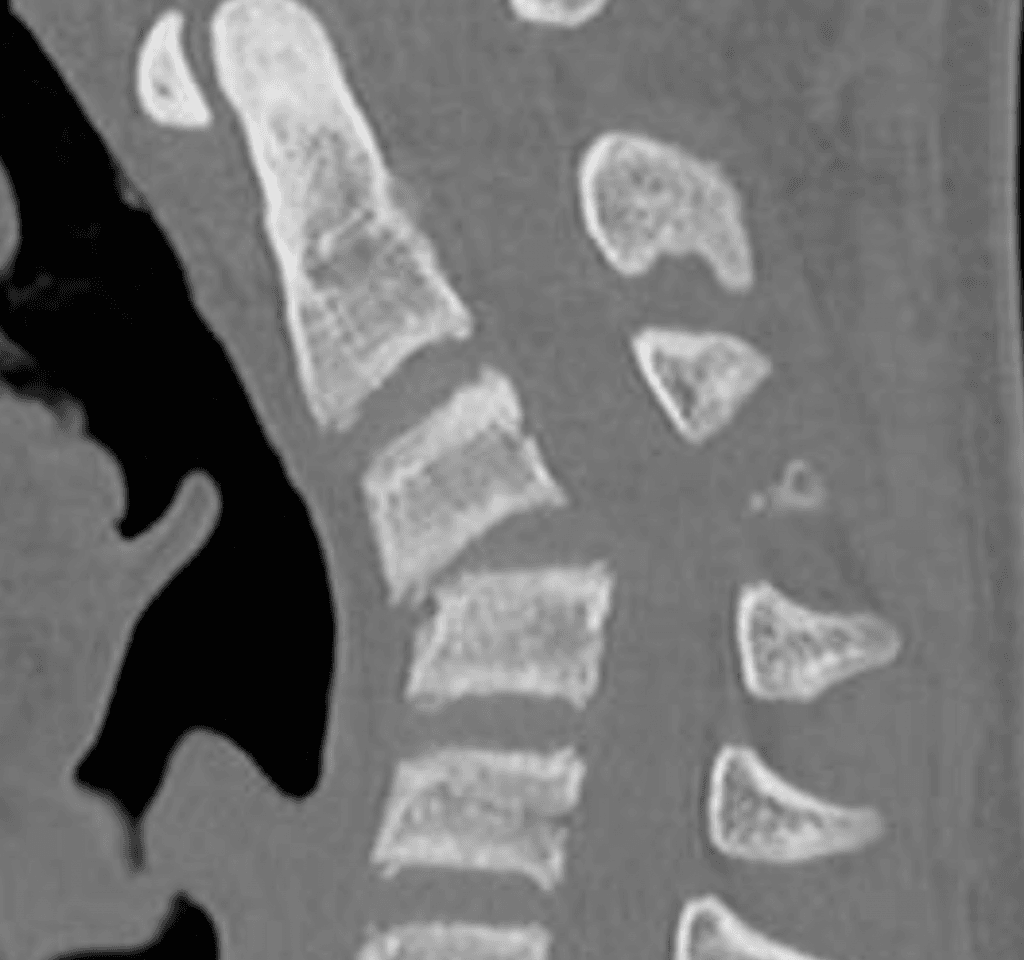

Fractura cervical tipo C con luxación facetaria

Masculino, 16

Antecedente de derrumbe en Scrum de rugby 40 días antes de la consulta. Cervicalgia intensa, refractaria al tratamiento médico conservador.